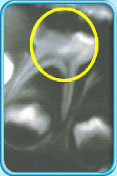

图中所见是一张X光片,显示一颗牙髓还没坏死的乳臼齿。治疗前